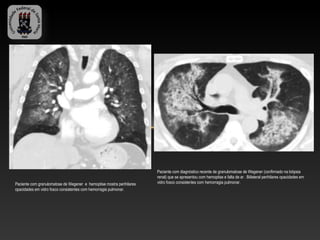

Paciente com diagnóstico recente de granulomatose de Wegener (confirmado na biópsia

renal) que se apresentou com hemoptise e falta de ar . Biilateral perihilares opacidades em

Paciente com granulomatose de Wegener e hemoptise mostra perihilares   vidro fosco consistentes com hemorragia pulmonar.

opacidades em vidro fosco consistentes com hemorragia pulmonar.